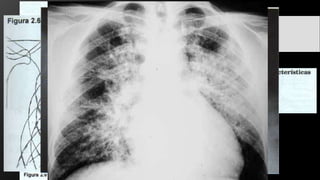

Neumonía Lobar

• Streptococcus Pneumonae.

• Cisuras interlobares bien definidas.

• Signo de la silueta.

• Broncograma aéreo.